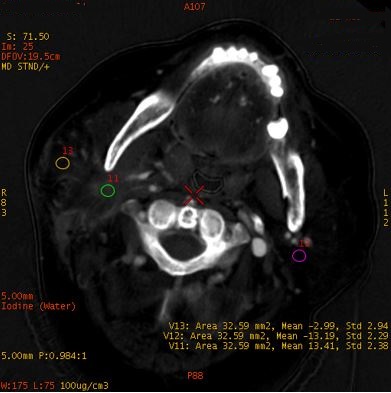

水基图

直方图

水基-直方图:直观显示了不同ROI面积下水含量的差异;感染病变侵犯的脂肪间隙的水含量高于正常脂肪间隙;感染病变与肌肉的水含量差异不大。